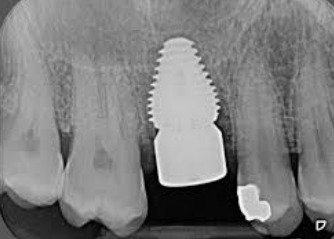

1단계 - 초기 상담: 환자는 치과 의사와 상담을 진행합니다. 의사는 어금니의 상태를 평가하고, X-레이나 CT 스캔을 통해 뼈의 상태를 확인합니다. 이를 토대로 의사는 어금니 임플란트가 적합한 치료 방법인지 판단하며, 필요한 어금니 임플란트 가격을 예상할 수 있습니다.

2단계 - 수술: 치과 의사는 어금니 부위에 조심스럽게 구멍을 내고 임플란트를 삽입합니다. 그 후, 임플란트 주위의 뼈와 임플란트가 안정적으로 결합되도록 치유를 위한 기간을 마련합니다. 이 과정은 일반적으로 수 주에서 몇 개월까지 소요될 수 있습니다.

또한, 어금니 임플란트 시술 후에는 10-20주 사이에 골유착 상태를 확인해야 합니다. 통증, 감염 여부, 출혈 여부, 임플란트 주변 뼈의 손실 여부 등을 확인하여 식립이 잘 되었는지 판단합니다. 이를 통해 어금니 임플란트의 성공 여부를 확인할 수 있습니다.